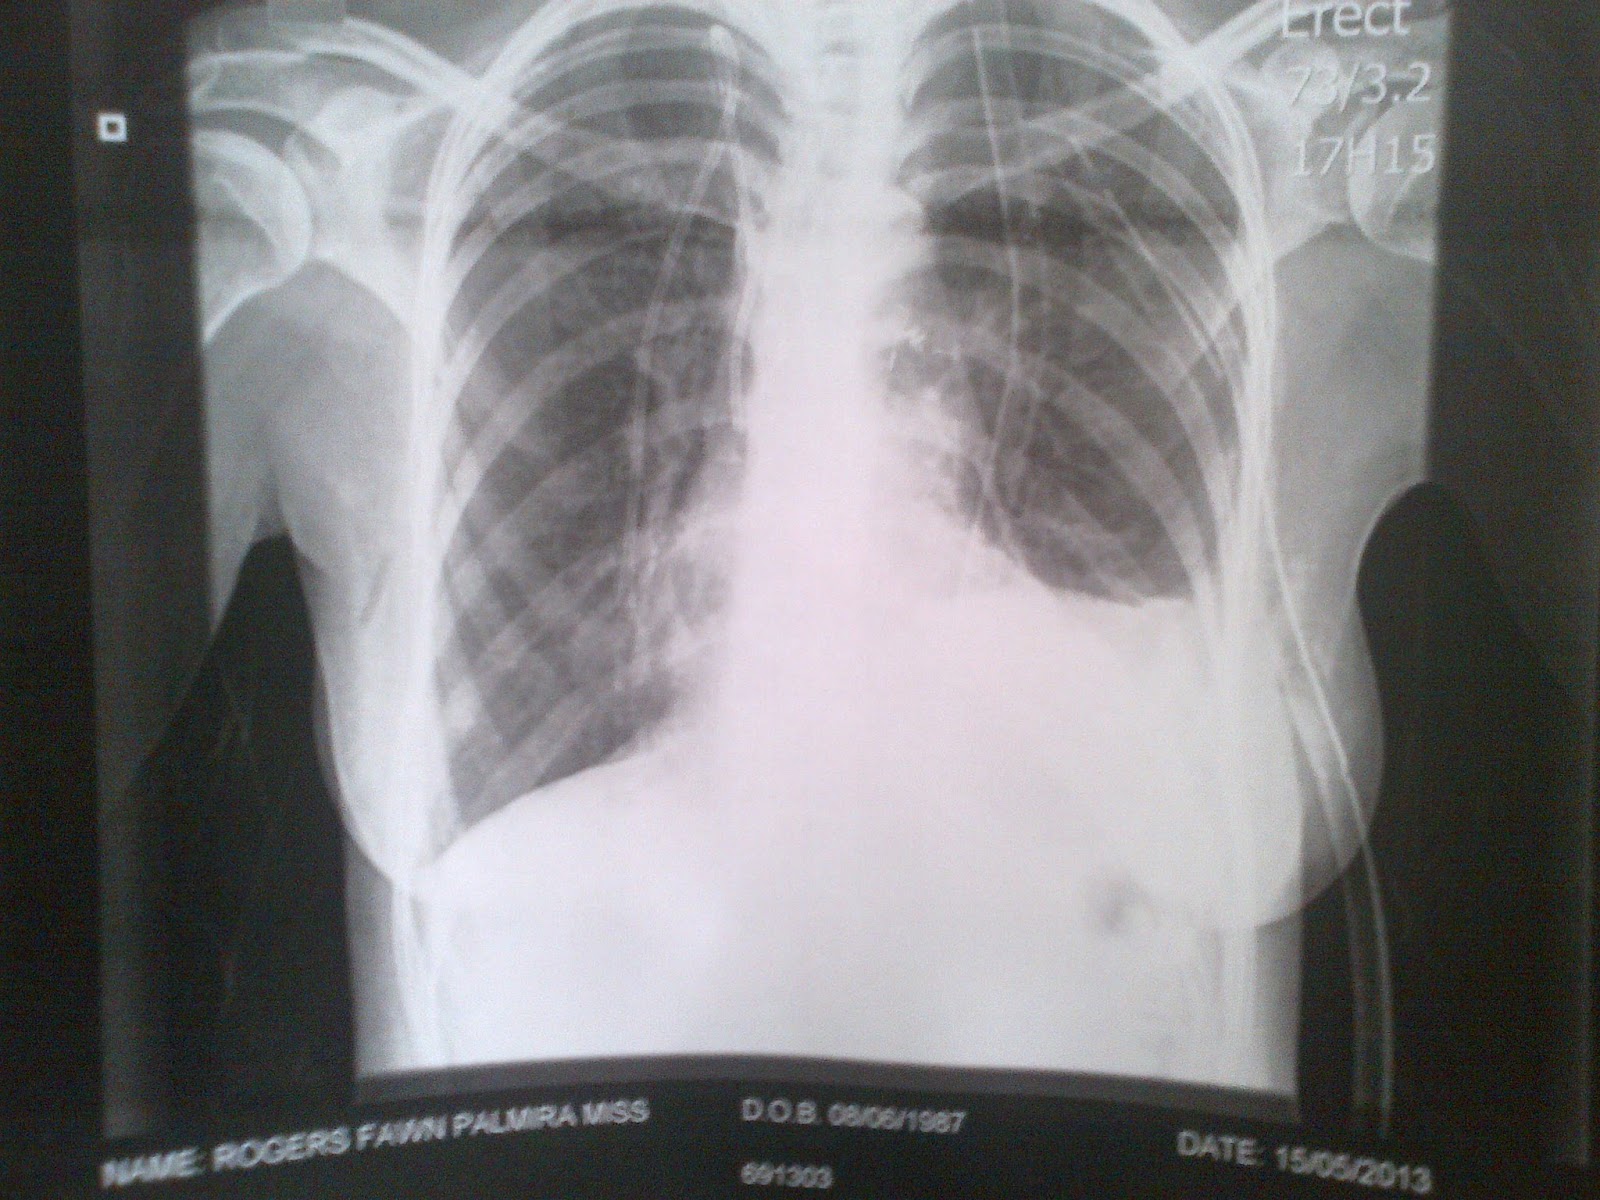

From www.deerdiary.co.za

Deer Diary Punctured Lungs Medical Name For Punctured Lung A pneumothorax is an accumulation of air or gas in the space between the lung and the chest wall that occurs when a hole develops in the lung that allows air to escape. Punctured lung is when air leaks from the lung cavity into the chest cavity, creating pressure on the lung and leading to collapse. In some people, a. Medical Name For Punctured Lung.